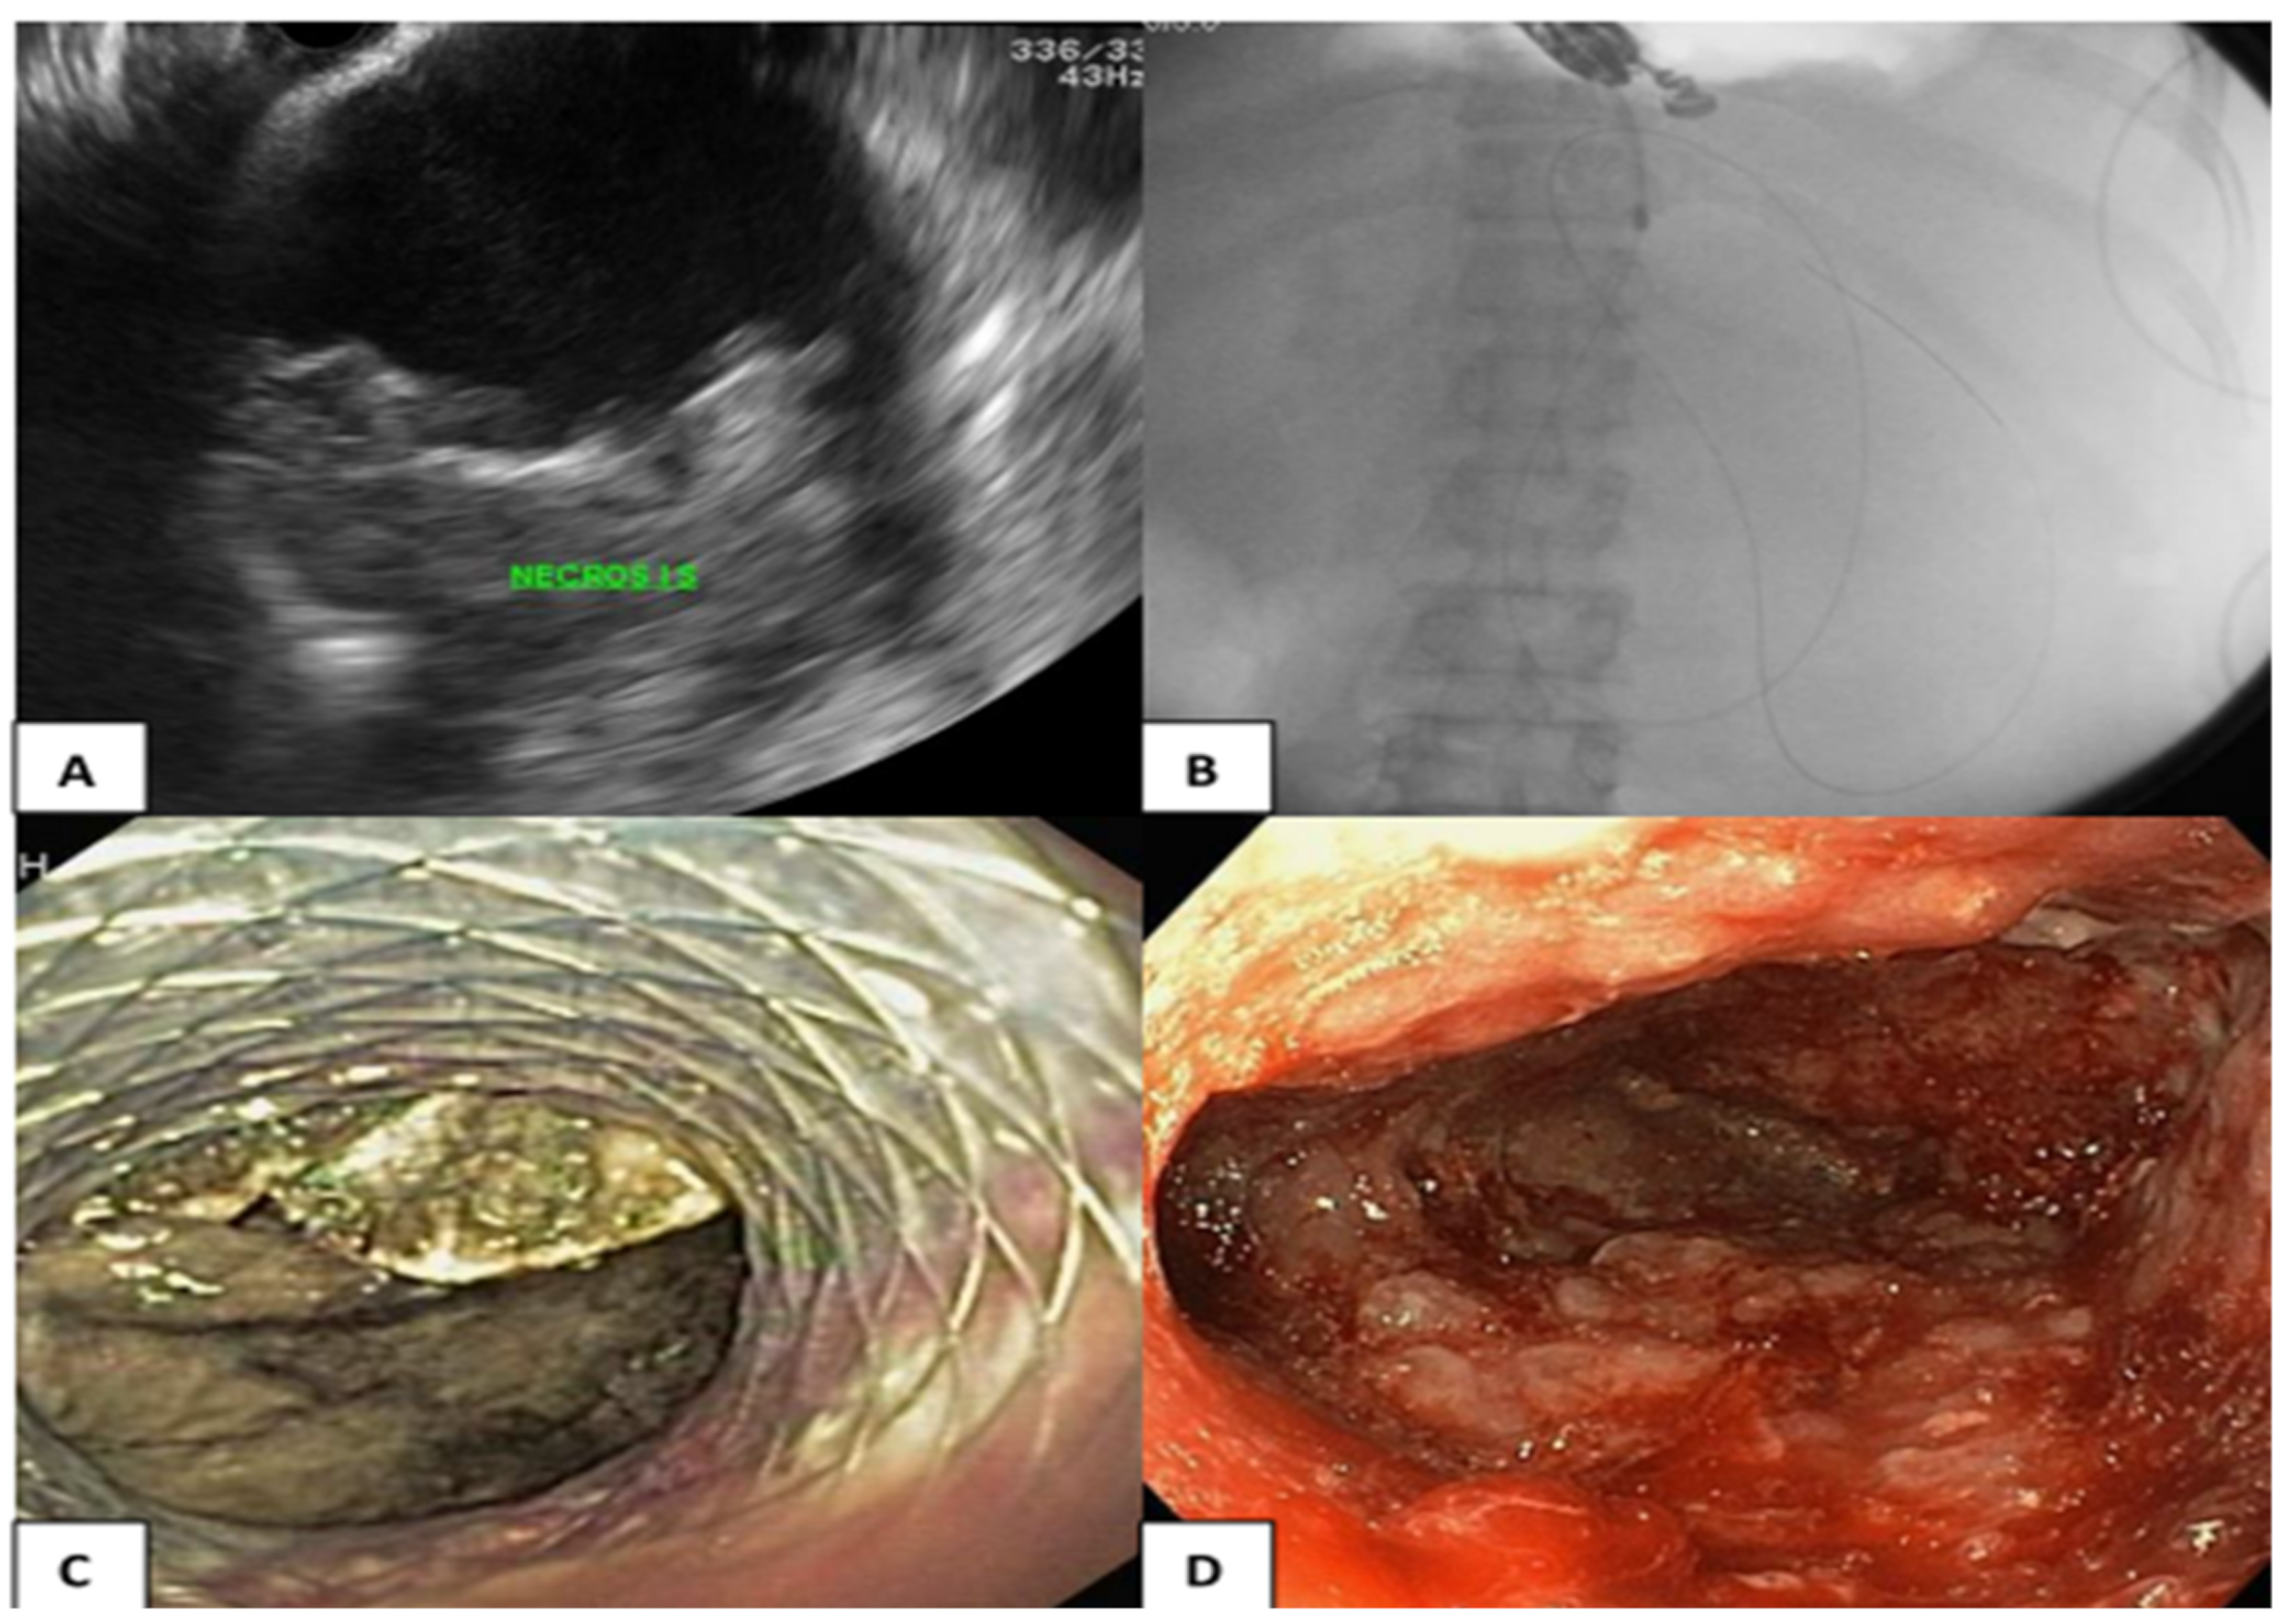

2.2. Endoscopic Transmural Drainage

2.3. Percutaneous Drainage

2.4. Directed Endoscopic Transmural Necrosectomy